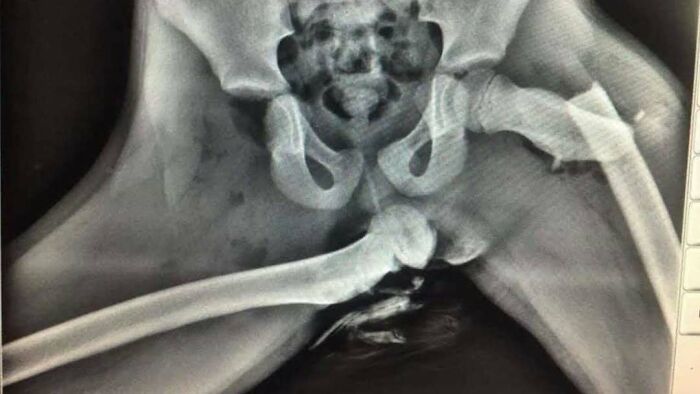

KUB X-ray shows two large and oval radio-opaque shadows in the pelvis

Image source: medical.doctors